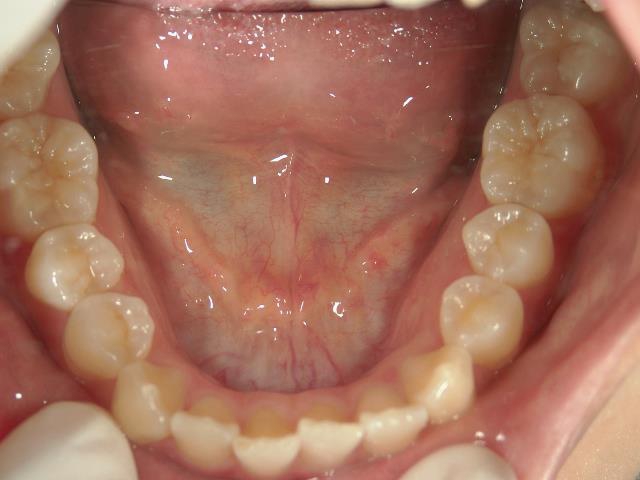

矯正歯科 治療前 下顎